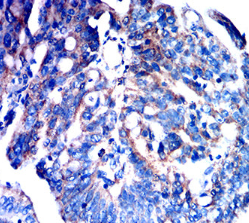

IHC    1/200 - 1/1000